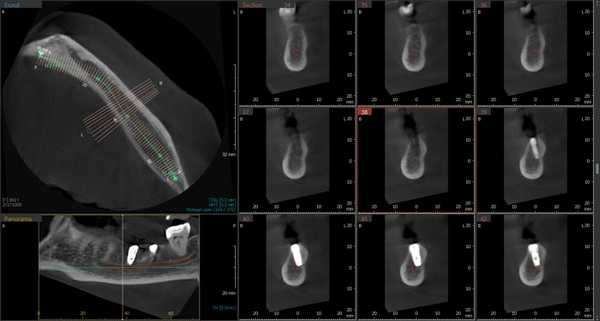

Рентгенологическое исследование проводилось на аппарате Galileos GAX5 («Sirona Dental Systems, Bensheim», Germany). Анализ полученных данных проводился по традиционной методике, предусматривающей последовательное изучение сначала срезов в 3 взаимно перпендикулярных проекциях (окно мультипланарной реконструкции), затем срезов, расположенных продольно и поперечно относительно зубной дуги (в окне «Панорама»), а также томограмм произвольной кросс-секции, оптимальной для получения изображений анатомических объектов соответственно их пространственному положению. Оптимальными для визуализации вариантов ветвления канала НЧ являлись реформаты вдоль продольной оси ее тела, которые обозначаются по терминологии разработчиков аппарата как «касательные».

Пациентка Ф., 55 лет. С правой стороны на уровне угла челюсти от верхней стенки нижнечелюстного канала начинался дополнительный канал с поперечным диаметром 1,52 мм (рис. 3, а). Рис. 3. Дентальный канал нижней челюсти. а — КЛКТ пациентки Ф., 55 лет; б — КЛКТ пациентки К., 29 лет. 1 — канал НЧ; 2 — дентальный канал; 3 — подбородочное отверстие. Поперечный диаметр основного канала на этом же уровне — 2,70 мм. Дополнительный канал направлялся полого вперед и вниз параллельно основному каналу НЧ. В мезиальном направлении кортикализация стенок дополнительного канала постепенно уменьшалась, и достоверно проследить его ход удалось до уровня зуба 4.7. Описанная картина характерна для дентального канала (3-й тип раздвоенного канала НЧ). С левой стороны визуализация дополнительного канала была недостоверной: выявлялось линейное просветление такой же локализации и направления, как с правой стороны, но картины трубчатого образования не выявлено, вероятнее всего — вследствие недостаточной кортикализации его стенок.

У пациентки К., 29 лет, с левой стороны обнаружен дентальный канал (см. рис. 3, б). В месте отхождения он имел вертикальный диаметр 1,35 мм (приблизительно в 3 раза меньше вертикального диаметра канала НЧ на этом же уровне), направлялся вперед и вниз, располагаясь параллельно основному нижнечелюстному каналу, и на уровне медиального корня зуба 3.7 круто поднимался вверх. Дентальный канал переставал идентифицироваться на уровне средней трети корня второго нижнего левого моляра. С правой стороны раздвоения канала НЧ не выявлено.